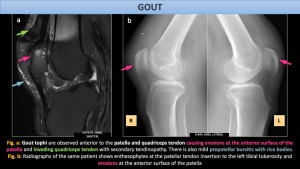

Gout: Gout is caused by the deposition of monosodium urate crystals in joints, soft tissues, and viscera. The knee joint may be involved. Depending on the sites of crystal deposition, gout can result in patellar erosions, patellar tendinopathy and bursitis[4].